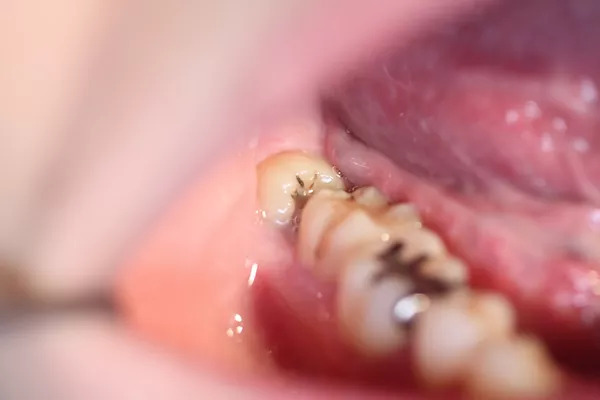

下の写真は、親知らずが横向きに生えていて隙間があります。

下の写真は、その隙間に食べかすが入ってしまっています。

この隙間は下の方が深歯ブラシが届かず、このままでは親知らずと手前の歯が2本とも虫歯になってしまうので抜いたほうが良いケースです。